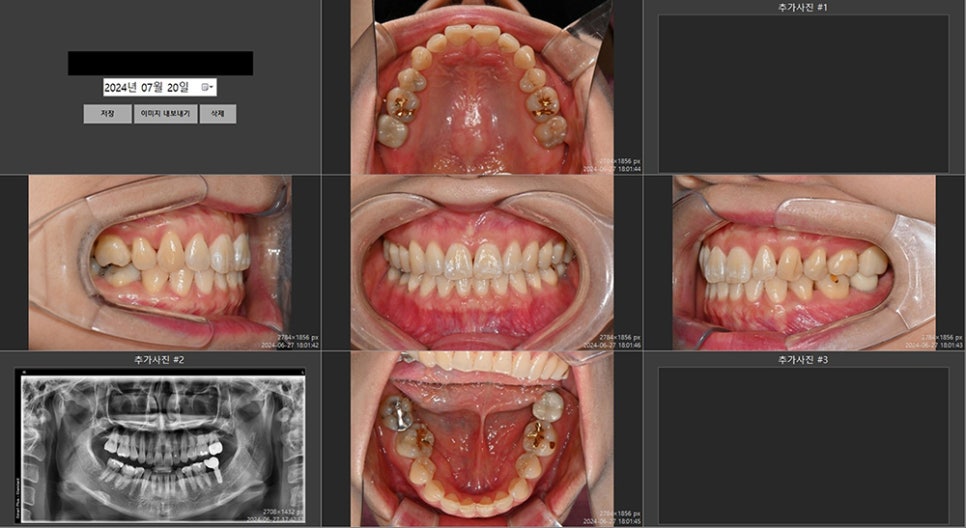

파노라마 촬영 및 구내 사진 촬영

문진표 작성 후 교정치과 연세정원치과에서는 먼저 전체적인 치아 상태를 알 수 있는 파노라마 사진과 구내 사진을 루틴하게 촬영한 후 상담을 시작합니다. 그냥 구강 검진만 한 후에 상담을 해드려도 되지만, 이렇게 환자분과 함께 본인의 구강 상태를 눈으로 확인하며 설명해드리면 환자분들 혹은 보호자분들께서도 잘 몰랐던 구강 내 상태를 조금 더 쉽게 이해를 하시더라구요.

파노라마 사진 및 구강사진

본인이 고치고 싶은 부분, 그 외에 현재 치료가 필요한 부분들과 가능한 치료 방법들을 설명드린 후 정밀 진단을 원하시는 경우 아래 7가지의 정밀 검사를 시행합니다.